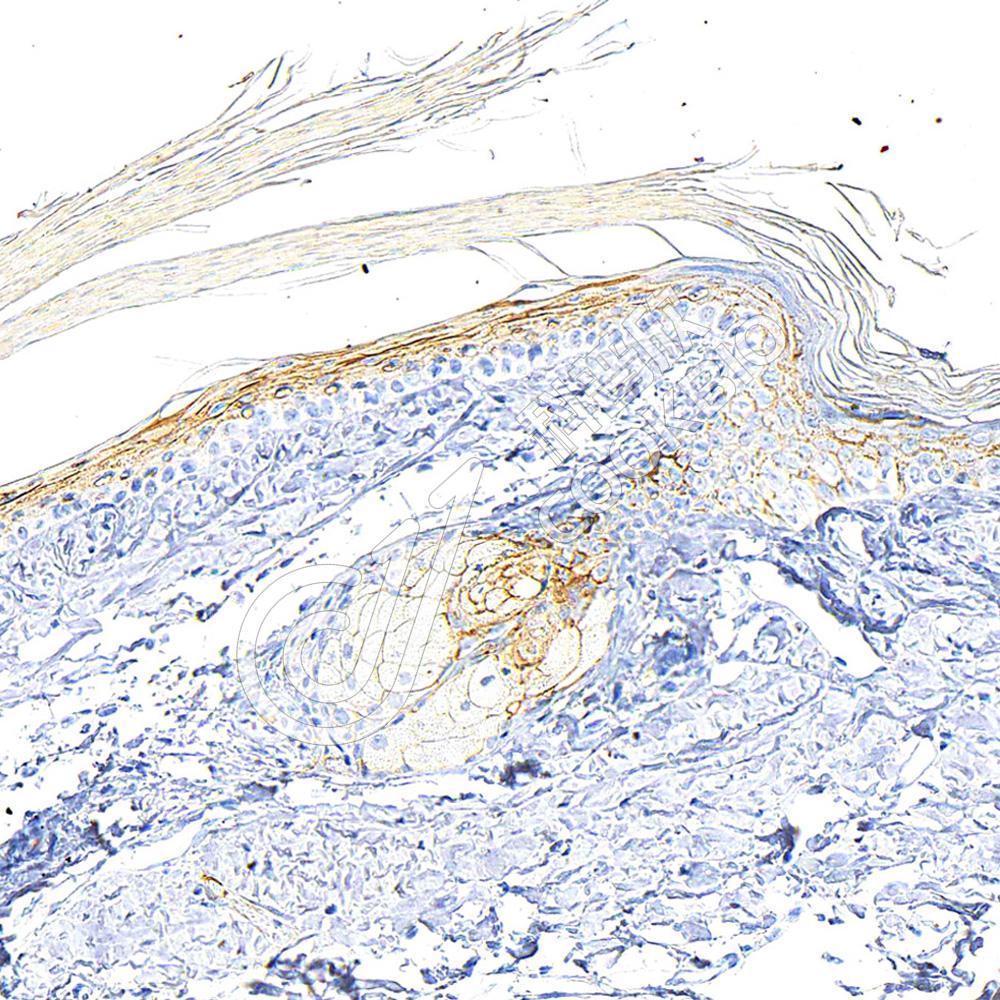

IHC检测E-cadherin蛋白(货号 K133246).

样品: 人食管, 4%多聚甲醛 (货号KSG1101) 固定12-24小时.

抗原修复: 柠檬酸抗原修复液(干粉, pH 6.0) (KSG1201), 98℃, 20分钟.

—抗: 1: 900稀释, 4℃ 孵育过夜.

二抗: S-vision免疫组化多聚二抗(山羊抗兔),即用型 (货号KB3906), 室温孵育20分钟.